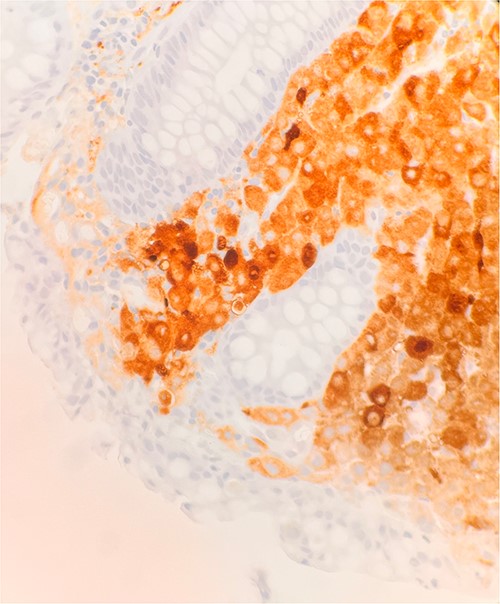

Microscopic examination shows extensive involvement of the bladder wall by sheets of small round blue tumor cells showing cleaved and irregular nuclear contours and conspicuous nucleoli. Mitotic activity is frequent and majority of cells show scant amphophilic cytoplasm with few foci showing more abundant bubbly cytoplasm and others with clear foamy cytoplasm (Fig. 1). A rare foci of finely granular brown pigment representing melanin and moderate cytological atypia in a small area of surface urothelium. Similar morphological features are seen in colonic biopsy specimens (Fig. 2).

Microscopic examination reveals sheets of round cell beneath unremarkable urothelium epithelium. H&E stain 40×.